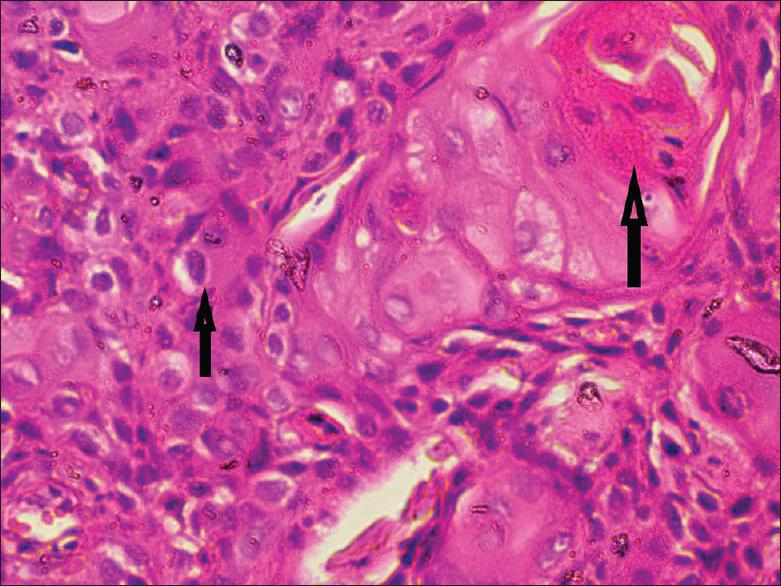

Necrotizing ulcerative periodontitis (NUP) is a painful and debilitating condition seen mostly in an immunocompromised state. Although squamous cell carcinoma (SCC) on gingiva is not uncommon, its presentation as a benign necrotizing lesion on gingiva is rare. Such presentations may lead to delayed diagnosis and poor prognosis. This report describes a case of a 34-year-old male presenting clinically with NUP around mandibular posterior teeth. Clinical features were misleading, but the histological findings established the diagnosis of well-differentiated SCC. Immunohistochemistry also showed features of epithelial-mesenchymal transition with decreased expression of E-cadherin and increased vimentin expression showing local invasion and metastasis. The patient was referred to the oncology department for evaluation of possible metastasis and further management of carcinoma.

坏死性溃疡性牙周炎(NUP)是一种主要见于免疫功能低下状态的疼痛性且使人衰弱的病症。虽然牙龈鳞状细胞癌(SCC)并不罕见,但其表现为牙龈上的良性坏死性病变则较为罕见。此类表现可能导致诊断延迟和预后不良。本报告描述了一例34岁男性患者,临床上表现为下颌后牙周围的NUP。临床特征具有误导性,但组织学检查结果确诊为高分化SCC。免疫组织化学还显示出上皮-间质转化的特征,E-钙黏蛋白表达降低,波形蛋白表达增加,提示局部侵袭和转移。该患者被转诊至肿瘤科,以评估可能的转移情况并对癌症进行进一步治疗。